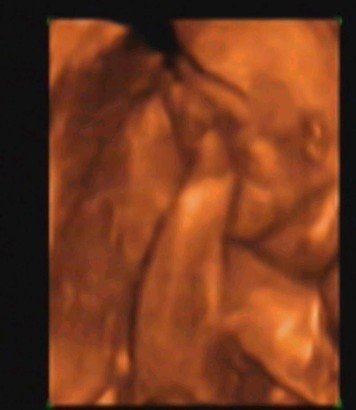

看四维的录像 这是小宝宝的鸡鸡吗 两腿中间的那个 点击展开 匿名用户 2013-11-08 18:20 满意回答 对的,就是这个,你太有才了 匿名用户 2013-11-08 18:20 宝宝知道提示您:回答为网友贡献,仅供参考。 相关问题 看四维录像,这是宝宝的小鸡鸡吗 今天做了四维大夫说正常,就是没看到小宝宝,别人做的都能看到我的怎么没有啊 今天做了四维大夫说正常,就是没看到小宝宝,别人做的都能看到我的怎么没有啊